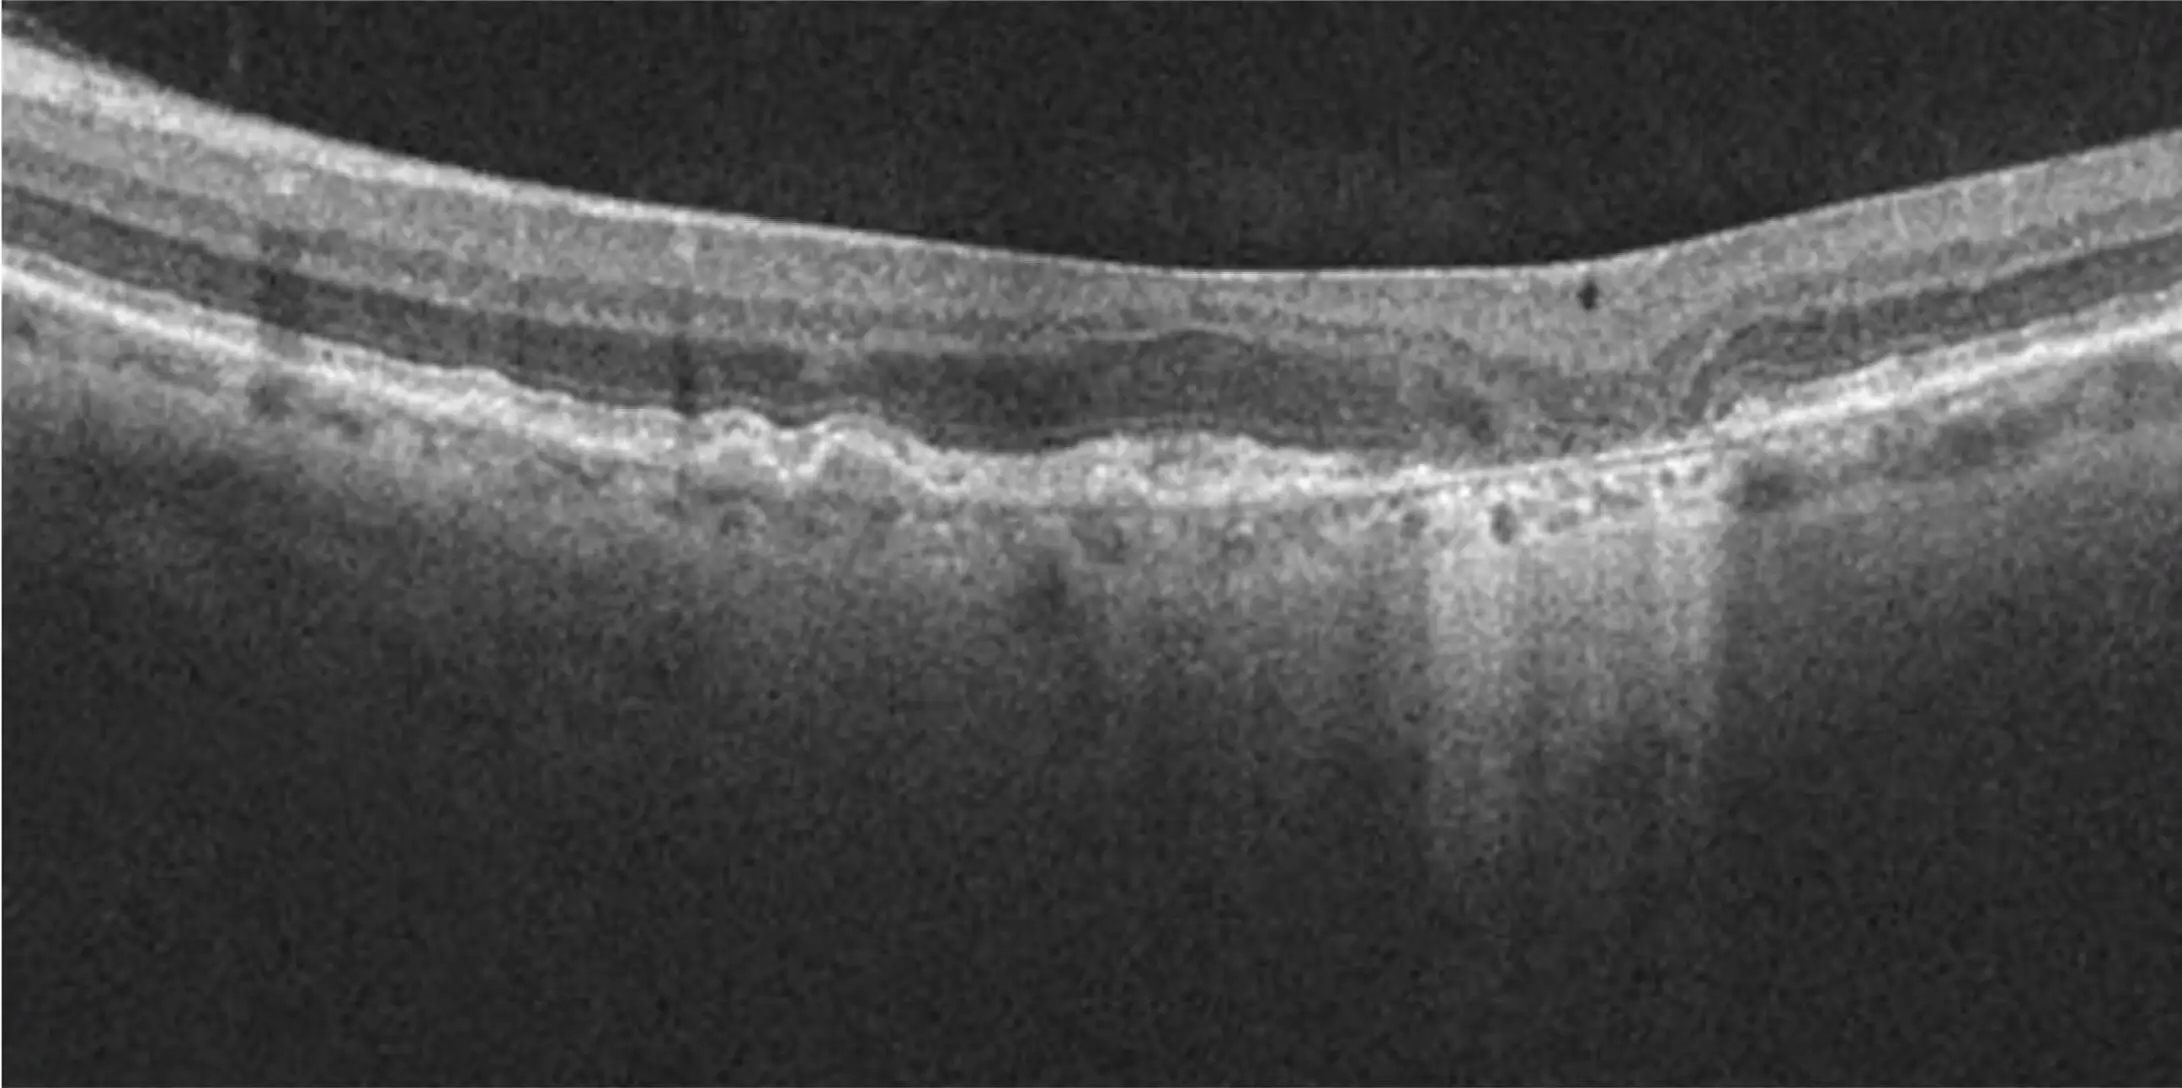

Optical Coherence Tomography (OCT)

Image courtesy of Dr. Mark Dunbar.

OCTEstablished as a key reference when assessing individuals for initial GA diagnosis9,10

Hypertransmission defects through the choroid point to areas of absent retinal pigment epithelium (RPE), photoreceptors (PR), and choriocapillaris layers.2